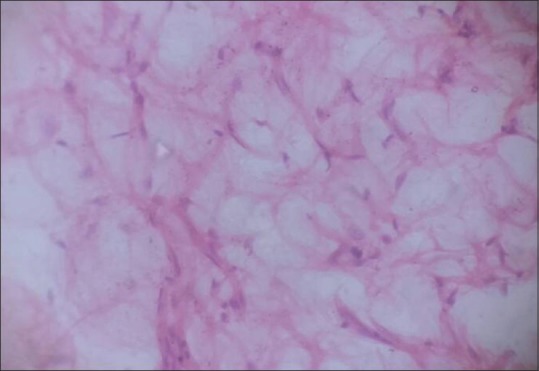

| Figure 6:Section shows abundant adipose tissue (H and E, ×400)

A 21-year-old right hand dominated female presented with a progressive disproportionate enlargement of distal arm and digits of the right hand since birth. The patient denied having any pain or neurovascular symptoms, and there was no family history of extremity gigantism. Twelve years back, she had a history of amputation of index and middle fingers at some periphery hospital. However, no records of the same were available. On physical examination, a nontender, soft-tissue mass was palpable on the volar aspect of the enlarged thumb with disfigurement of digits and distal arm [Figure 4]. There were no overlying cutaneous changes, pitting edema, or bruit. A plain radiograph demonstrated soft-tissue swelling along the volar aspect of the thumb, enlarged phalanges of the digits [Figure 5]. Gray-scale ultrasound and color flow Doppler revealed diffuse soft-tissue thickening, without any abnormal calcifications or abnormal blood flow. Fine-needle aspiration from the disproportionate areas yielded blood-tinged fatty aspirate. Smears examined revealed fragments of mature adipose tissue. No malignant cells were identified. No other spindle cell component was identified. The background revealed fat droplets admixed with RBCs and few inflammatory cells. Correlating the lesion's clinical presentation, imaging and cytological finding possibility ML was considered. The multidisciplinary team decided to perform a debulking surgery. On gross examination a yellowish soft-tissue mass was received which on cut section was fibrofatty. No firm areas or hemorrhage or necrosis was identified. Microscopic examination revealed mature fibroadipose tissue involving the subcutaneous plane [Figure 6]. The nerve sheath and the surrounding muscle fibers were free of fatty infiltration. Thus, a definitive diagnosis of ML was rendered which confirmed the initial possibility.